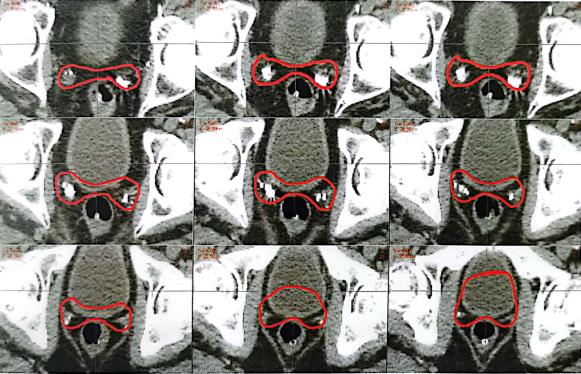

靶区勾画图示

A

B

C

A.耻骨联合以上水平横断面术后瘤床勾画;B.耻骨联合以下水平横断面术后瘤床勾画;C.矢状位和冠状位图像

图1-1 前列腺癌术后瘤床勾画注:1.上界一般在耻骨联合上3~4cm以内,包括输精管残端及前列腺瘤床。2.耻骨后方包全,侧界至闭孔内肌或肛提肌,后界至直肠前壁。3.下界勾画至膀胱尿道吻合口下8~12mm或尿道球上缘水平。